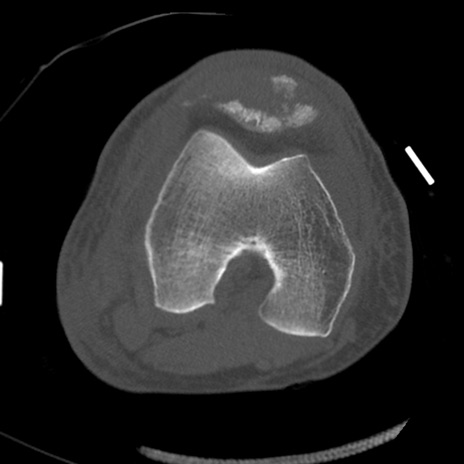

症例28 右膝関節CT(横断像)

右膝関節CT